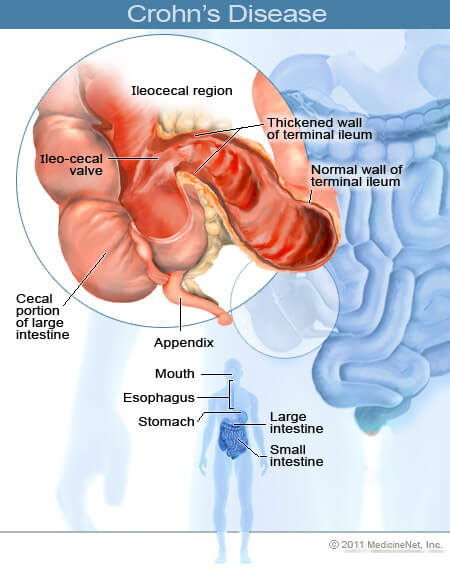

Антибиотик, използващ се за лечение на чернодробна енцефалопатия и диария на пътуващите, дава обещаващи резултати при лечението на болестта на Крон (БК).

Антибиотик, използващ се за лечение на чернодробна енцефалопатия и диария на пътуващите, дава обещаващи резултати при лечението на болестта на Крон (БК).

Авторите коментират, че е крайно време да се открие метод за лечение на БК чрез механизми, които не изискват потискане на имунната система. Според настоящата хипотеза за патогенезата на заболяването, в интестиналния тракт се наблюдава промяна в микрофлората, която уврежда чревната лигавица, което от своя страна води до активация на имунитета. Базирайки се на тези предположения, изследователите решили не да потиснат имунния отговор, а да елиминират причините за тази активация.